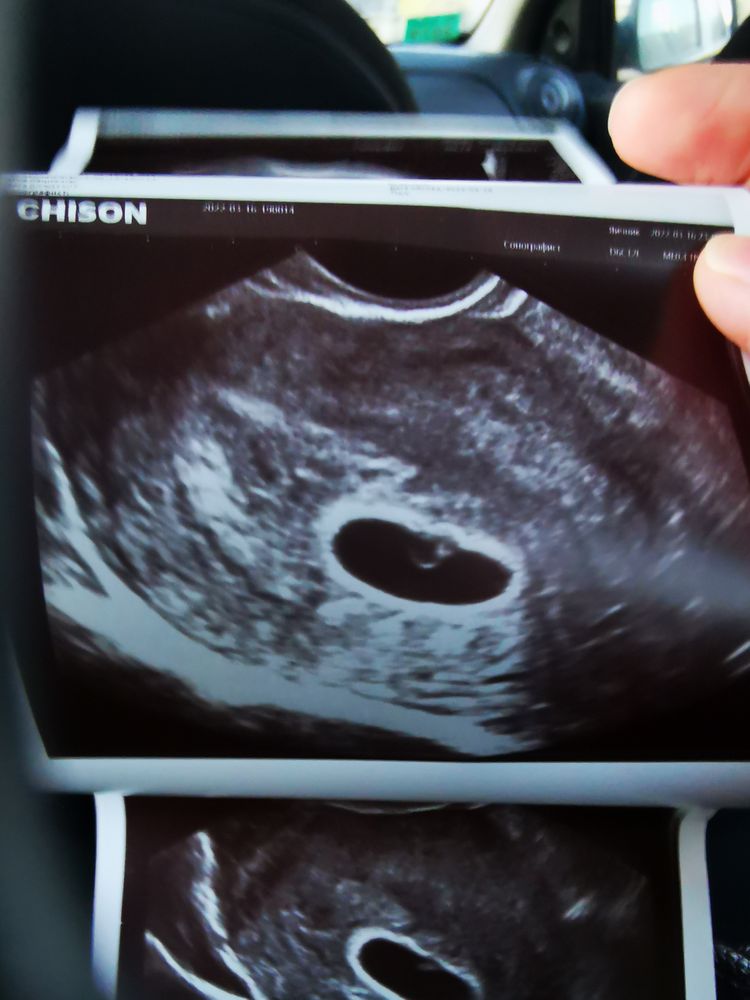

Изображение 6 недель